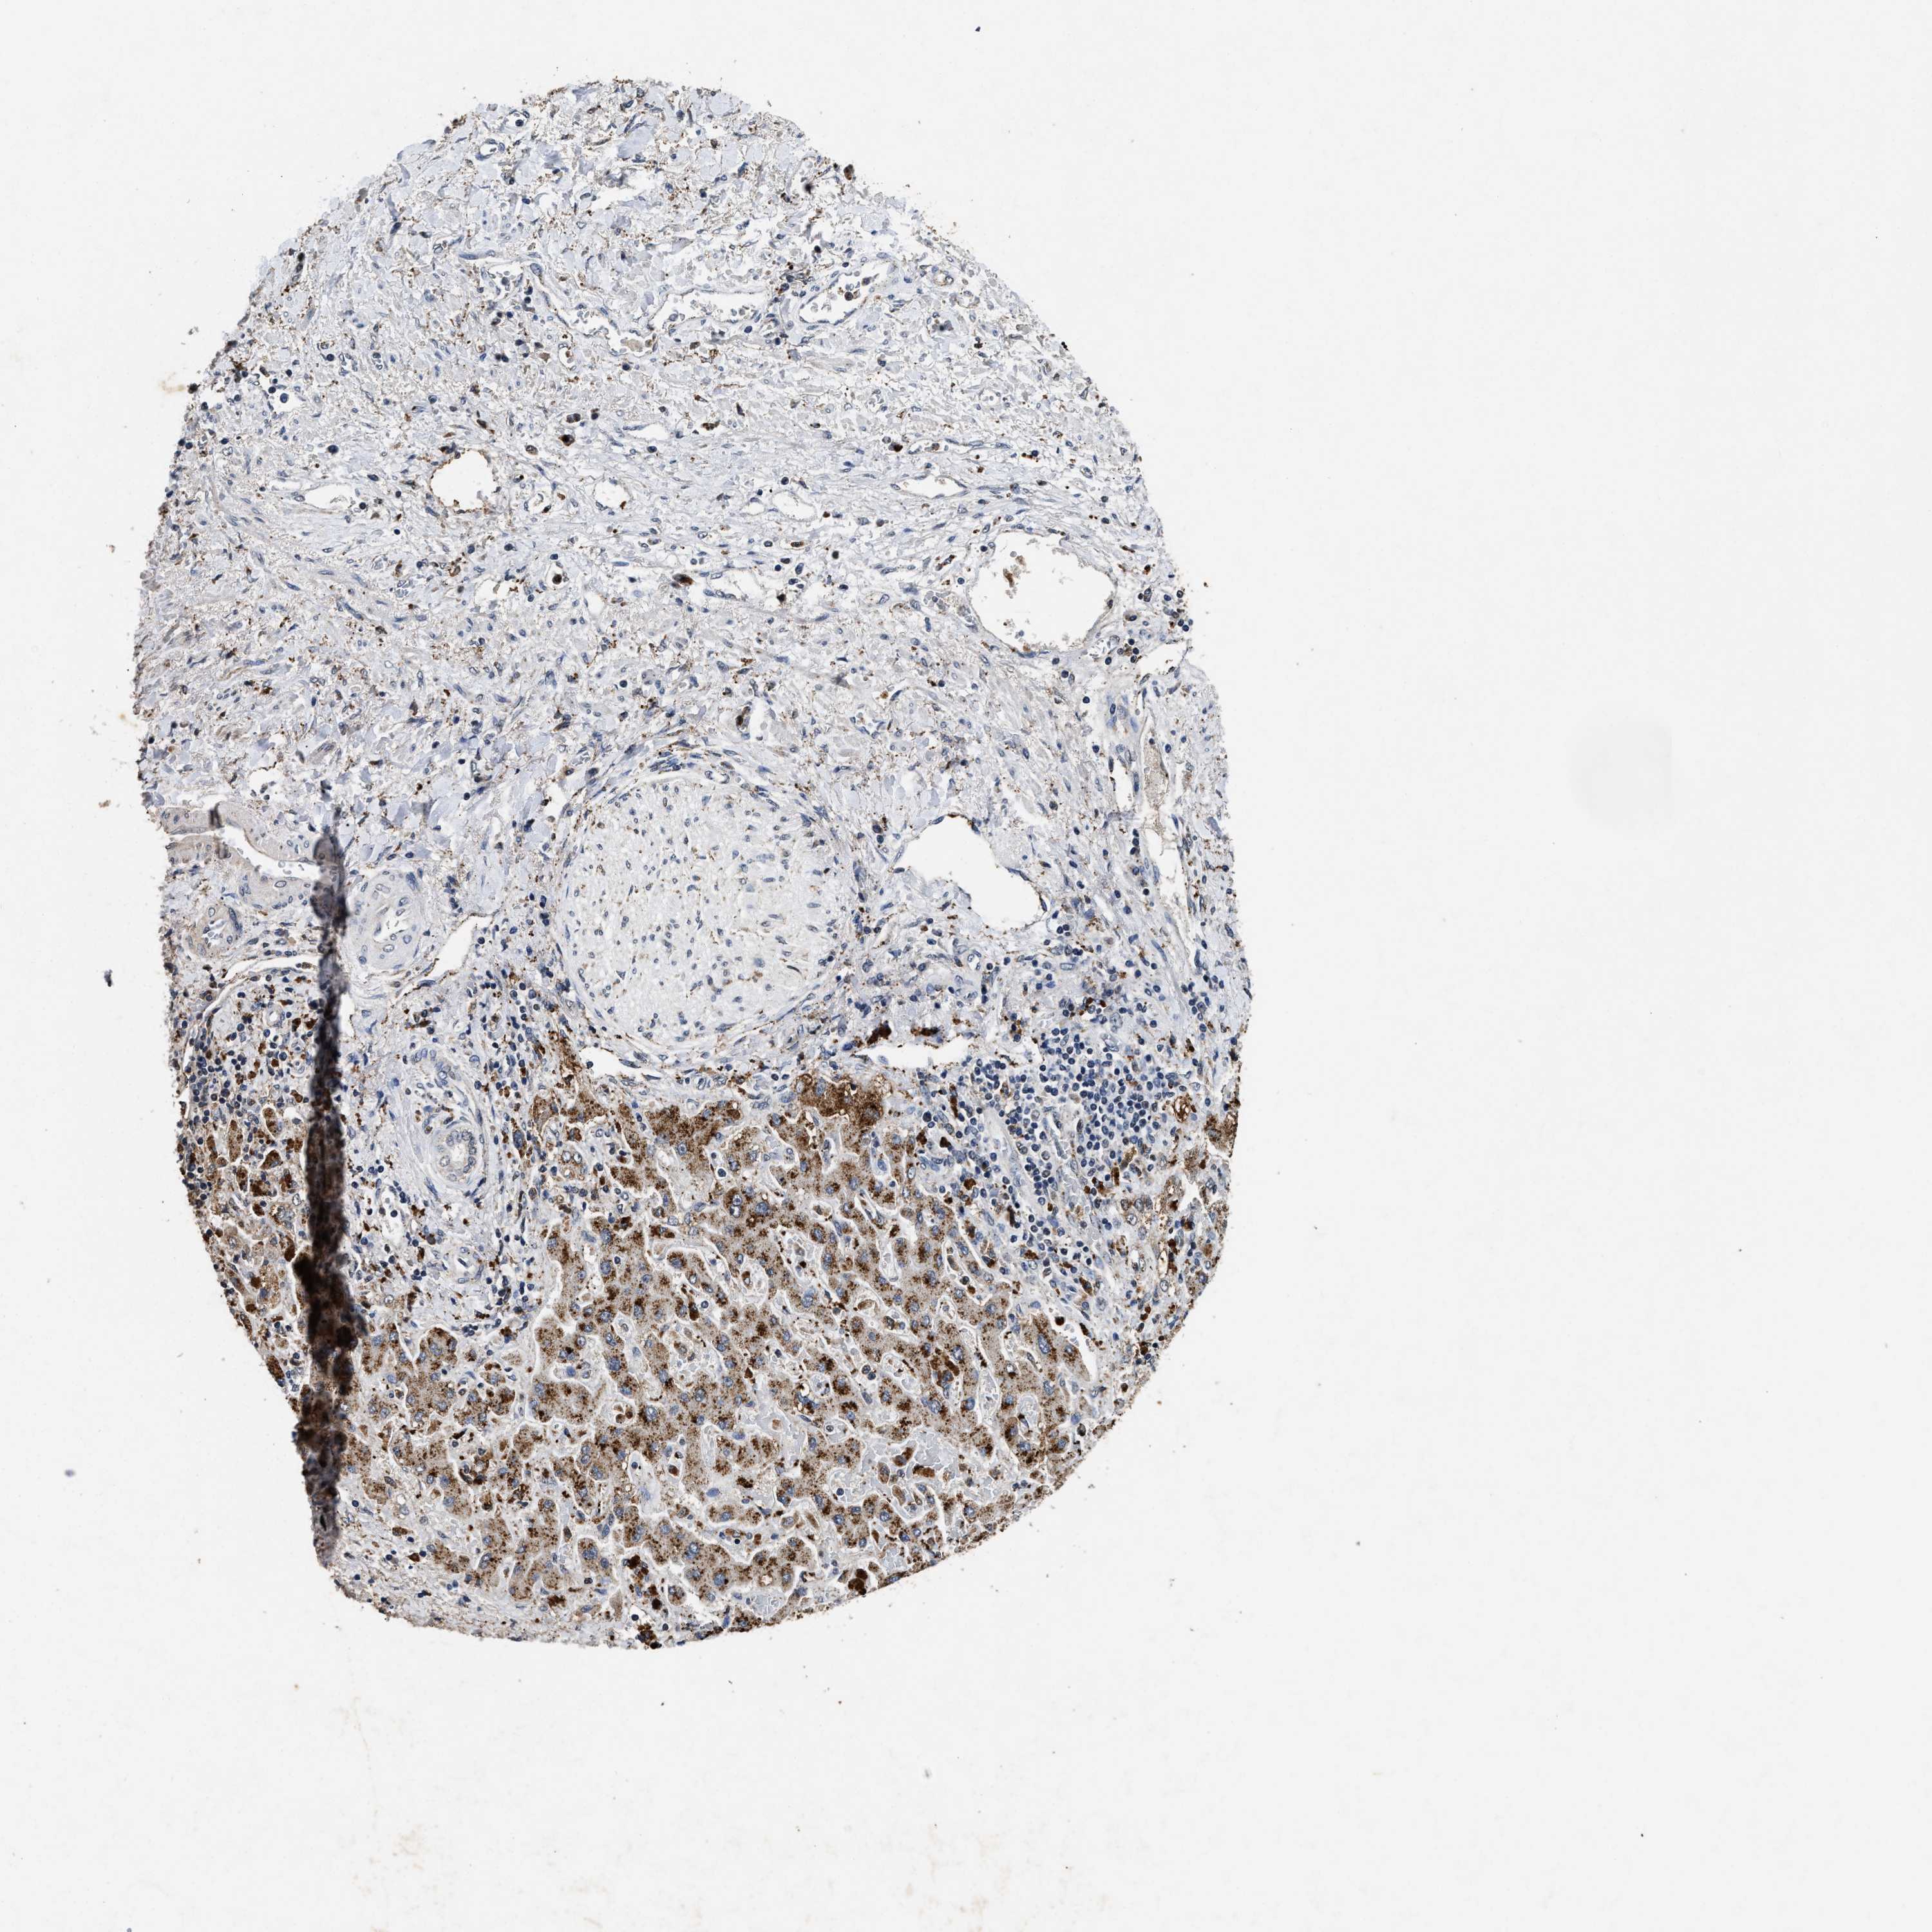

LIVER CANCER - Protein expressioni

A mouse-over function shows sample information and annotation data. Click on an image to view it in a full screen mode. Samples can be filtered based on level of antibody staining by selecting one or several of the following categories: high, medium, low and not detected. The assay and annotation is described here.

Note that samples used for immunohistochemistry by the Human Protein Atlas do not correspond to samples in the TCGA dataset.

Antibody stainingi

Antibody staining in the annotated cell types in the current human tissue is reported as not detected, low, medium, or high, based on conventional immunohistochemistry profiling in selected tissues. This score is based on the combination of the staining intensity and fraction of stained cells.

Each image is clickable and will lead to virtual microscopy that enables deeper exploration of all samples and also displays staining intensity scores, fraction scores and subcellular localization as well as patient and tissue information for each sample.

Antibody HPA021192

Antibody HPA021195

Antibody HPA028759

Antibody CAB021094

Staining

High

Medium

Low

Not detected

Intensity

Strong

Moderate

Weak

Negative

Quantity

>75%

75%-25%

<25%

None

Location

Nuclear

Cytoplasmic/membranous

Cytoplasmic/membranous,nuclear

Cholangiocarcinoma

Carcinoma, Hepatocellular, NOS